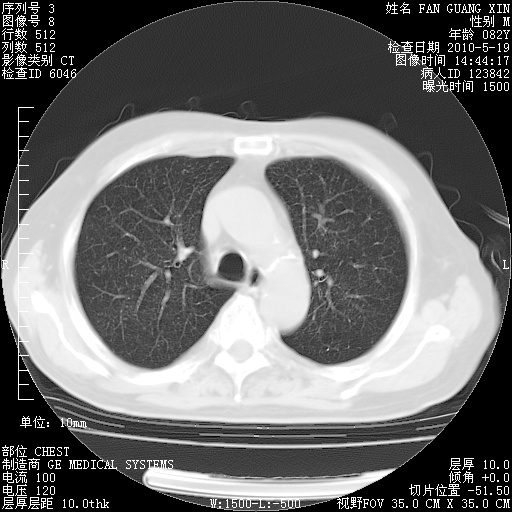

可改为口服强的松40-50mg/d治疗,若病情仍稳定,胸部阴影不再吸收可逐渐减量